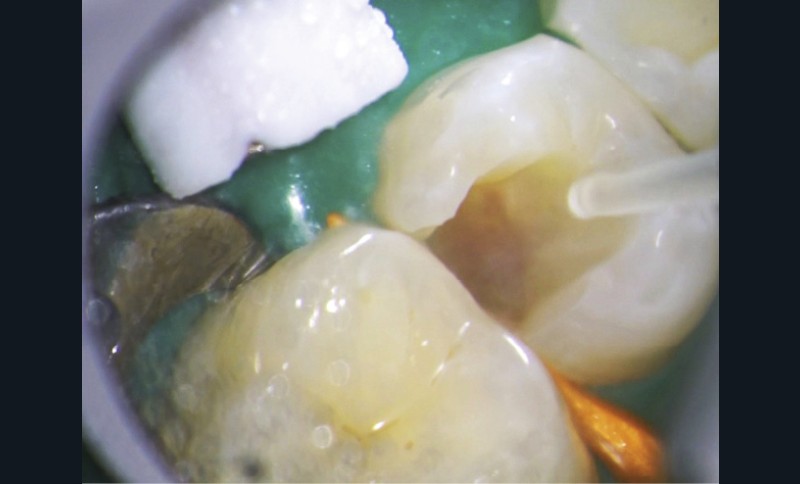

L’exposition pulpaire a deux causes principales : traumatique ou carieuse.

Dans le cas d’un traumatisme récent, chez le jeune ou l’adulte, la pulpe doit être systématiquement coiffée pour conserver la vitalité pulpaire

Concernant les coiffages sur dents adultes, un bon diagnostic doit être posé pour faire le bon choix entre la conservation pulpaire totale, partielle ou le traitement endodontique [34]. Il est particulièrement indiqué chez le jeune dont les dents immatures ont une édification apicale incomplète.

Plusieurs facteurs interviennent dans le bon pronostic du coiffage pulpaire : l’élimination de l’inflammation, le contrôle de l’infection et la biocompatibilité des matériaux utilisés [35].

Le laser Er:YAG va permettre une élimination des débris en surface, une stérilisation, avec comme irrigation de l’eau stérile [36] et en coupant le spray, une hémostase avec la formation d’une couche de coagulation [37] propre à la formation d’un pont dentinaire au contact du biomatériau, qui peut être bio-actif, tel que la Biodentine (Septodont) (fig. 6a à d).

Protocole opératoire : sous anesthésie, une cavité suffisante à recevoir le biomatériau (2 à 3 mm) sous champ opératoire est réalisée. La désinfection au laser Er:YAG (40 mJ ; 20 Hz) sous spray, pendant 20 secondes, est alors mise en œuvre. S’en suit éventuellement une coagulation de 3 secondes, en coupant le spray, puis la mise en place du biomatériau Biodentine (Septodont). Il sera ensuite recouvert d’un matériau de restauration adéquate.